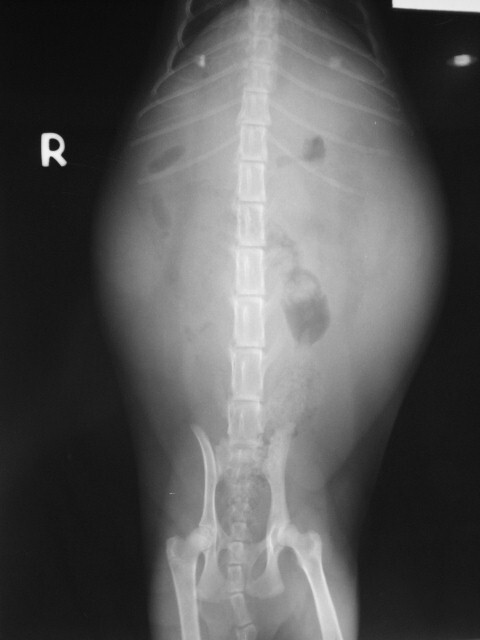

主題: 五甲南京路口 腹膜炎有腹水的貓咪 申請者姓名: 劉雅雲 花色: 申請日期: 2012-11-10 01:27:48 申請者部落格: 申請者臉書網址: 所在縣市/合作醫院: 高雄市/樂生動物醫院 治療費用: 6850元 需求人數: 8人 已結案 (2013-06-27 14:03:00) 報名人員: kelly(已付款)、MeiDan Wang(已付款)、Sky(已付款)、Sky(已付款)、Sky(已付款)、Sky(已付款)、Sky(已付款)、Sky(已付款)、 候補人員: 動物病情說明: 這是在五甲南京路誘捕結紮的貓咪, 麻醉後醫生發現貓咪有腹水的現象, 所以進行血檢與腹膜炎的檢驗. 在治療照顧下, 貓咪已抽過一次腹水, 但還是不敵腹膜炎的病魔, 當天使去了.

Fip貓的費用如下:

驗血 1500

貓FIV/FELV KIT 500

台灣基因貓FIP血液檢查_1550

穿刺放液術(腹腔)_600

住院__300 * 9 =2700 <10/23 - 10/31>

TOTAL=6850